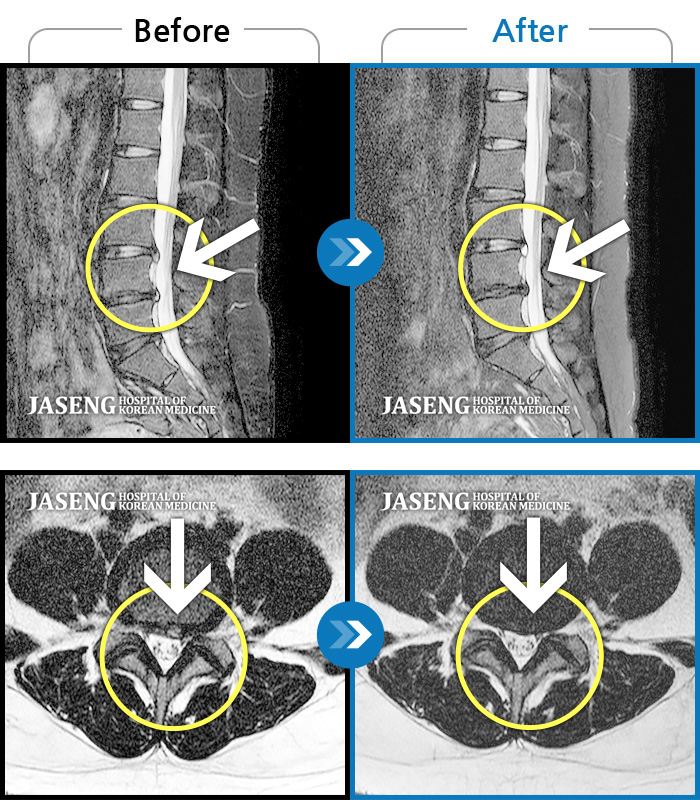

허리디스크

인천 · 강아현 원장

우측 허리 통증 및 다리 저림이 심하여 앉거나 바로 눕는 것도 힘든 상태로 내원하셨습니다. 감각 저하도 동반되어 심각한 신경손상이 의심되는 상황이었습니다.

촬영시기

2024.07.27 ~ 2025.04.05

2025.04.16

조회수 351